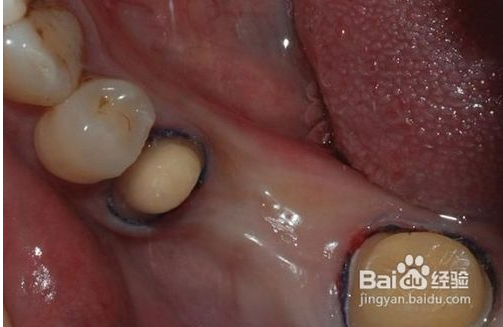

1、磨牙

為了使完成后的烤瓷牙冠戴入后不超過原始狀態(tài)的外牙厚度,一般做烤瓷牙要磨除部分自然牙。另外為了使假牙順利就位并獲得良好的固位,要將基牙制備成一定的形狀?;乐苽涞暮脡?,關(guān)系到假牙是否容易戴入以及牢固性。